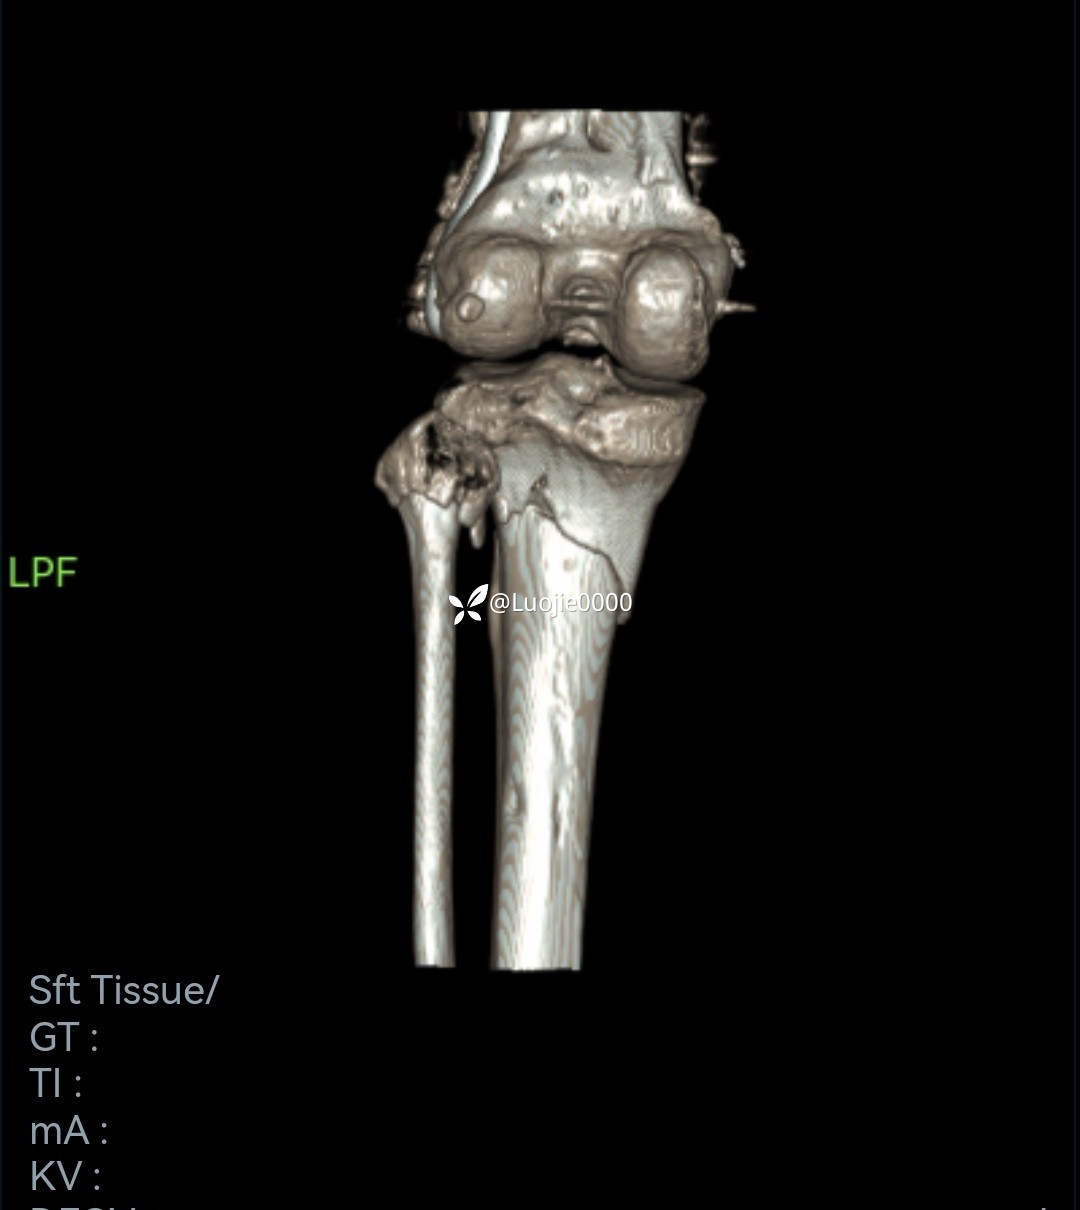

辅助检查:DR及CT提示:左胫骨近端及腓骨头骨折。

影像资料如下: